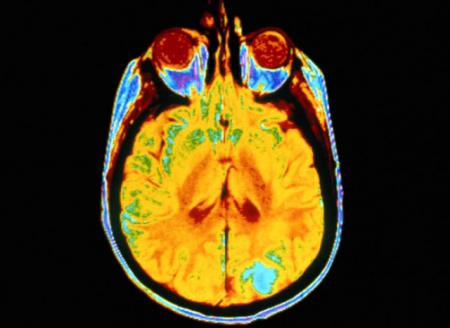

Manželka , Mamka - je po ťažkej operácii tumoru v hlave , operáciu podstúpila v Prahe , nakoľko bol tumor uložený vo veľmi ťažko prístupnom a životu ohrozujúcom priestore . Napriek úspešnej operácii niekedy stráca videnie a stabilitu . Invalidný manžel po troch operáciach chrbtice je bez možnosti zamestnať sa . Rodina sa dostáva do hlbokej krízy a ich tri deti potrebujú ešte pomoc .

Ale vráťme sa k tomu , prečo som túto výzvu napísal , vráťme sa o niekoľko mesiacov naspäť ........ keď manželke v máji diagnostikovali tumor v oblasti mozgovej artérie a očných nervov o veľkosti skoro 4x3x1,5 cm .... nechceli sme tomu uveriť , aj keď príznaky toho sa objavili už skôr . Človek si stále nepripúšťa to najhoršie a neverí , až keď sa nezačal kolotoč vyšetrení a konzultácií s neurológmi a neurochirurgom . Bála sa manželka a bál som sa aj ja , keď nám povedali že sa ten tumor nachádza v ťažko prístupnej oblasti a klasickou operáciou by mohlo dôjsť k devastačným poškodeniam mozgu , rozhodli sme sa pre operáciu Lekselovým Gama nožom v Prahe , nakoľko Slovensko nedisponuje takouto stereotaktickou technikou . Je to menej invazívna metóda , ale náročná na liečenie a rekonvalescenciu . Celková doba liečenia po týchto zákrokoch je 2 - až - 5 rokov . V celkovom sledovaní je pacient ďalších 5 rokov takže povedať že sme vyhrali môžme až po 10 - tich rokoch .